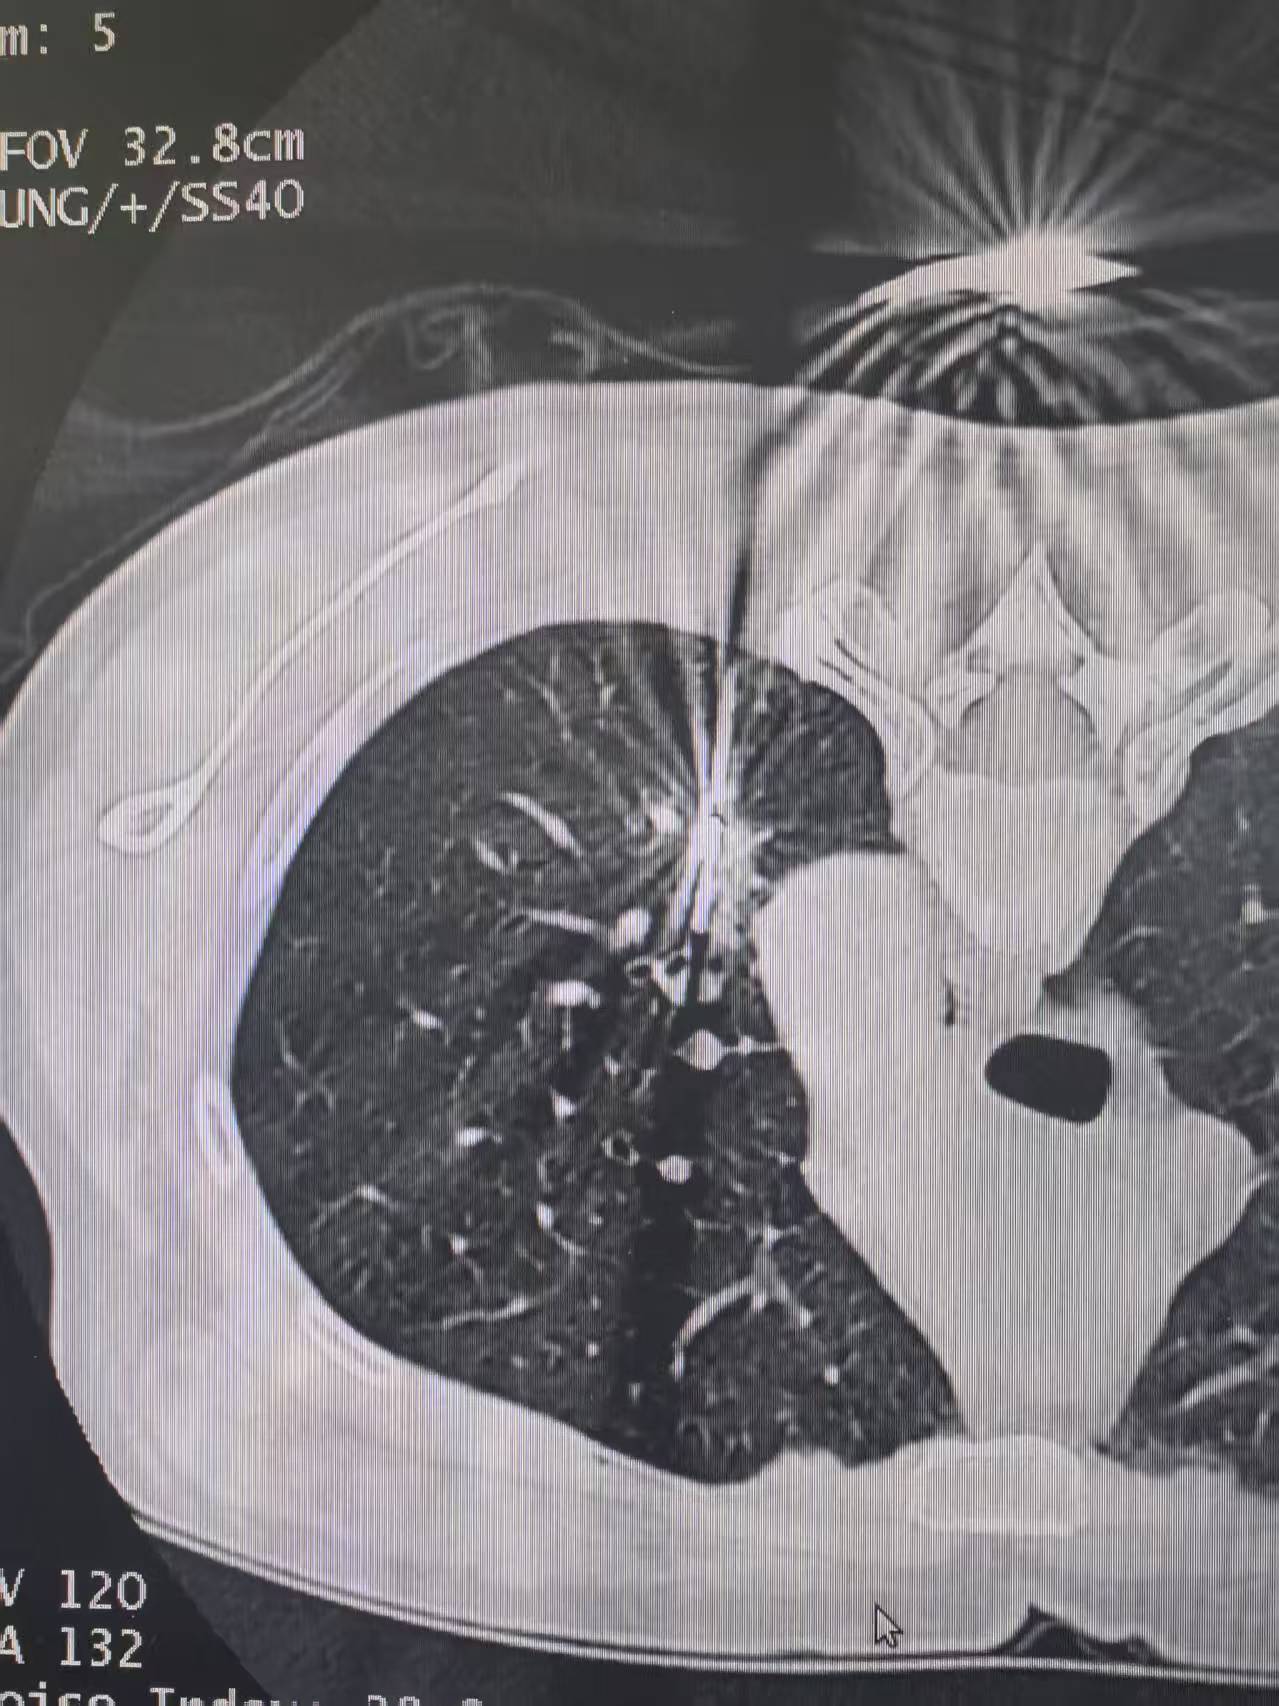

左下肺实性肺癌。左下肺实性肺癌,清扫了第4-14组淋巴结……对于实性的...

这个8mm的微浸润腺癌,看了很多地方没看出来,我们团队没有漏掉这个恶性...